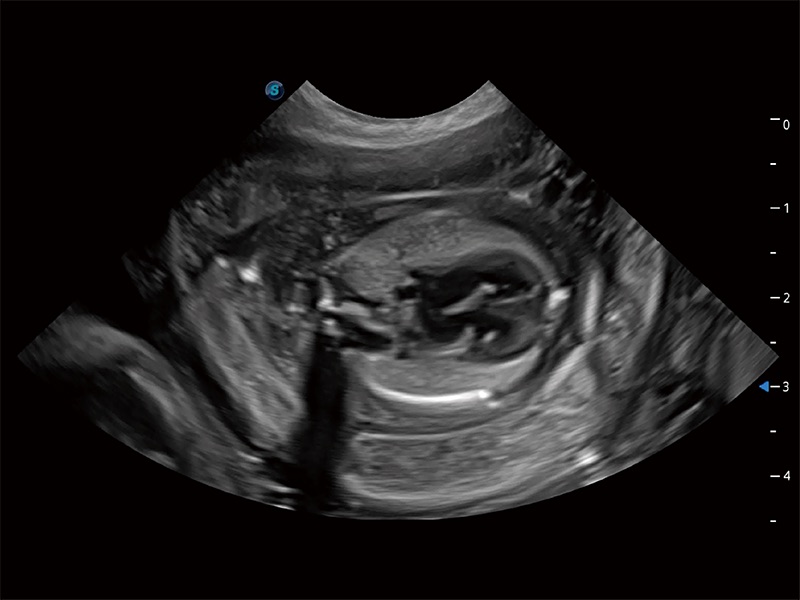

動物是人類最親密的朋友和最值得信賴的伙伴。開立醫(yī)療也一直致力于探索動物專用的超聲影像解決方案。全新推出的ProPet系列,是開立在動物超聲影像智能化、專業(yè)化、精準(zhǔn)化的一次跨越式革新。動物不能用言語來表述自己的不適,通過超聲影像,ProPet系列搭建了動物醫(yī)生與不同物種溝通的“橋梁”,為動物醫(yī)生注入了“治愈之力”。 ProPet 80 是開立醫(yī)療匠心打造的一款高端動物專用彩超,采用性能卓越的全新硬件架構(gòu),極大提升超聲系統(tǒng)的運(yùn)行效率和數(shù)據(jù)處理能力,幫助動物醫(yī)生從容應(yīng)對日益增多的挑戰(zhàn)性病例和日益多樣化的臨床需求。

ProPet 80 全新的動物超聲智能軟件和豐富的探頭群,為動物醫(yī)生提供了高清晰度和精細(xì)分辨率的圖像,無論在寵物、馬科、畜牧還是實(shí)驗(yàn)室動物等應(yīng)用中都可以輕松應(yīng)對,為您的日常工作帶來滿意的體驗(yàn)。